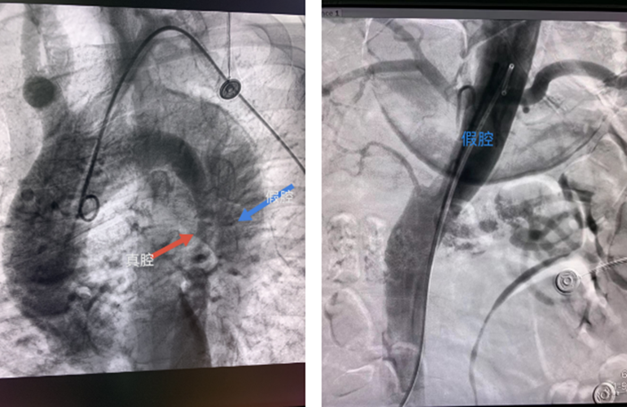

根据患者病史、体征及相关检查,完善胸腹主动脉CTA检查,结果提示:主动脉夹层DebakeyⅢ,胸腹段假腔大于真腔,假腔基本完全造影剂填充,假腔向下延及双侧髂外动脉近端,患者的病情已十分的严重,有手术指征。主动脉夹层,通俗讲就是主动脉上鼓起了一个像“瘤子”一样的东西,如果血压过高,主动脉容易从这里“溃堤”。这种疾病危险性非常高,时间久了,裂口会越撕越大,累及心脑肝肾等主要器官,甚至出现猝死。省心血管病医院九科欧阳长生团队,就患者的病情进行术前讨论,布置精密的手术操作计划,与家属进行充分的沟通,于入院次日在局麻下行主动脉覆膜支架腔内隔绝术。

因患者主动脉破口降主小弯侧,破口大,全程假腔大真腔极小,远端破口多,夹层累及双侧髂动脉,左肾、腹腔干真假腔供血,右肾及肠系膜真腔供血,手术难度大。手术过程非常紧张,功夫不负有心人,终于在右髂探寻到极小真腔影,在JR导管下泥鳅及J型都无法进入,欧阳长生灵机一动改用PTCA导丝进入,小心造影证实真腔后建立轨道,顺利完成隔绝,患者术后情况良好,返回病房。

欧阳长生总结:上下都被假腔挡道情况下术中操作要极为轻柔,轻柔冒烟寻找真腔入口,JR导管可调整方向,加PTCA导丝可以进入小腔。